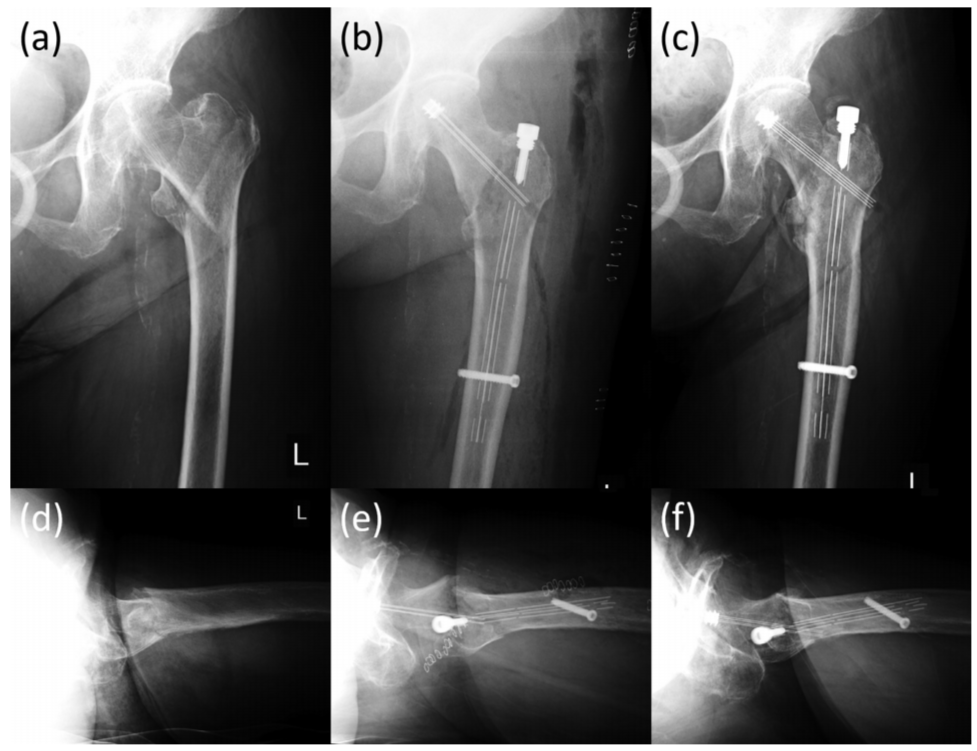

图3 一例92岁股骨粗隆间骨折患者,可见在正位片及侧位片上,骨折均良好显示。